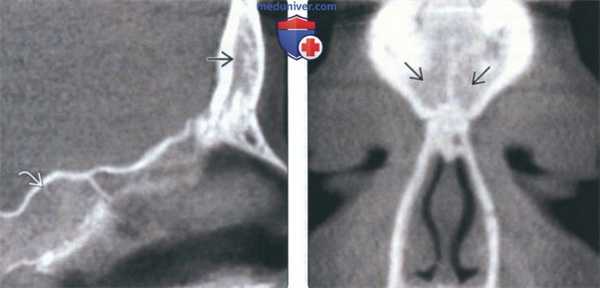

(Слева) На аксиальной КЛКТ справа и слева визуализируются добавочные устья ниже уровня соответствующих крючковидных отростков. Основные устья находятся на другом уровне и не видны на этом срезе.

(Справа) На корональной КЛКТ у этого же пациента визуализируются дополнительные устья справа и слева. Основные устья на этом срезе не видны. Обратите внимание на субтотальное снижение пневматизаци левой верхнечелюстной пазухи.

(Слева) На корональной КЛКТ (реконструкция) визуализируется добавочное переднее устье.

(Справа) На корональной КЛКТ визуализируются добавочные устья В, расположенные за основными. Картина сопоставима с таковой после хирургического вмешательства по поводу хронического синусита. Определяется утолщение слизистой оболочки В обеих верхнечелюстных пазух, обусловленное хроническим воспалением.